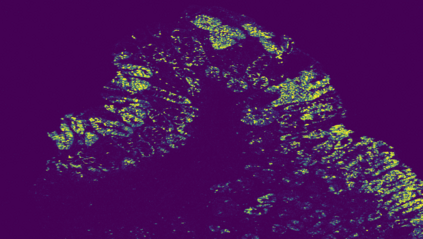

The usage of chemical imaging technologies is becoming a routine accompaniment to traditional methods in pathology. Significant technological advances have developed these next generation techniques to provide rich, spatially resolved, multidimensional chemical images. The rise of digital pathology has significantly enhanced the synergy of these imaging modalities with optical microscopy and immunohistochemistry, enhancing our understanding of the biological mechanisms and progression of diseases. Techniques such as imaging mass cytometry provide labelled multidimensional (multiplex) images of specific components used in conjunction with digital pathology techniques. These powerful techniques generate a wealth of high dimensional data that create significant challenges in data analysis. Unsupervised methods such as clustering are an attractive way to analyse these data, however, they require the selection of parameters such as the number of clusters. Here we propose a methodology to estimate the number of clusters in an automatic data-driven manner using a deep sparse autoencoder to embed the data into a lower dimensional space. We compute the density of regions in the embedded space, the majority of which are empty, enabling the high density regions to be detected as outliers and provide an estimate for the number of clusters. This framework provides a fully unsupervised and data-driven method to analyse multidimensional data. In this work we demonstrate our method using 45 multiplex imaging mass cytometry datasets. Moreover, our model is trained using only one of the datasets and the learned embedding is applied to the remaining 44 images providing an efficient process for data analysis. Finally, we demonstrate the high computational efficiency of our method which is two orders of magnitude faster than estimating via computing the sum squared distances as a function of cluster number.